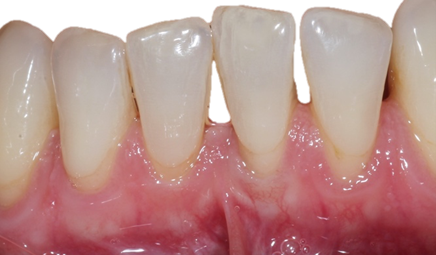

![]() | ![]() |

| Untreated severe gum disease | Gum disease treated and stabilised by Dr Halai |